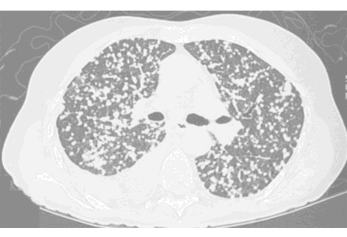

SHAPE - round

MARGIN - smooth

SIZE - 1-2 mm

DENSITY - can't tell on these CT windows (lung windows)

NOTE: any round lung opacity that is less than 3 cm in diameter can be called a 'NODULE'